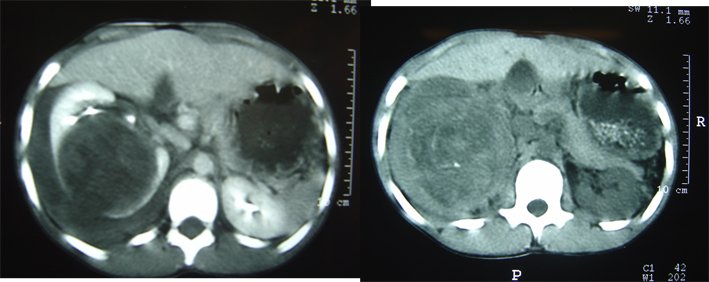

Case 4: A 12-year-old male, was refered to our hospital after being treated conservatively for renal trauma elsewhere for three days. The patient fell from a tree. CT is shown at Figure-3. Suspecting of a ruptured renal tumor, laparotomy was performed and showed a ruptured and bleeding right renal mass (Figure-4). Pathology revealed a renal carcinoma. Postoperative period was uneventful and the patient is alive and disease-free one year after the end of treatment.

Figure 3 - CT of case 4: peri-renal hematoma due to ruptured renal carcinoma.